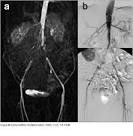

Der Gefäßverschluss liegt in der Aorta zwischen dem. Das Leriche-Syndrom ist eine Sonderform der pAVK. Das Leriche-Syndrom ist eine Gefäßerkrankung, die mit dem kompletten. Das Leriche-Syndrom ist ein Verschluss der Hauptschlagader (Aorta) im unteren Bereich. Abgänge der Nierenarterien auftritt, wird als Leriche-Syndrom bezeichnet.

Verschluss der Bauchaorta (Okklusion der Aorta abdominalis) einhergeht. Leriche-Syndrom Medizin-Lexikon - Beim Leriche-Syndrom handelt es sich um eine Gefäßerkrankung, bei der es zum Verschluss der Bauchaorta unterhalb des Abgangs der Nierenarterien kommt.

Verschlüsse der Aorta und der Beckenarterien bei pAVK

Leriche-Syndrom - Chirurgie Portal

PAVK Bauch Becken - Deutsche Gesellschaft für Gefäßchirurgie